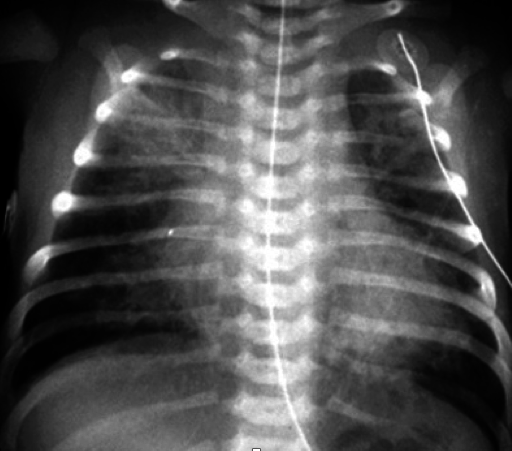

Which pediatric disorder will present with hyperinflation, patchy infiltrates and coarse streaking on chest x-ray? _____

Which pediatric disorder will present with overaeration, prominent pulmonary vascular markings and fluid in interlobar fissure on chest x-ray? _____